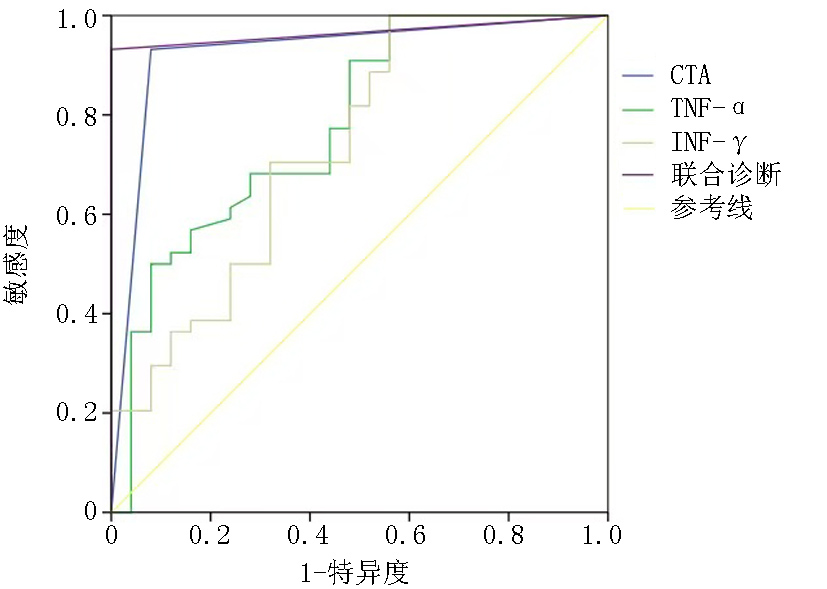

| 预测项目 | AUC | P值 | 95%可信区间 | 敏感度 | 特异度 | |

|---|---|---|---|---|---|---|

| 下限 | 上限 | |||||

| CTA | 0.926 | <0.001 | 0.850 | 1.000 | 0.932 | 0.920 |

| TNF-α | 0.780 | <0.001 | 0.662 | 0.897 | 0.909 | 0.520 |

| IFN-γ | 0.735 | 0.001 | 0.607 | 0.862 | 1.000 | 0.440 |

| 联合诊断(串联) | 0.966 | <0.001 | 0.921 | 1.000 | 0.932 | 1.000 |

Tab.5 The predictive value of a joint diagnostic model for carotid artery plaques in patients with ischemic stroke

| 预测项目 | AUC | P值 | 95%可信区间 | 敏感度 | 特异度 | |

|---|---|---|---|---|---|---|

| 下限 | 上限 | |||||

| CTA | 0.926 | <0.001 | 0.850 | 1.000 | 0.932 | 0.920 |

| TNF-α | 0.780 | <0.001 | 0.662 | 0.897 | 0.909 | 0.520 |

| IFN-γ | 0.735 | 0.001 | 0.607 | 0.862 | 1.000 | 0.440 |

| 联合诊断(串联) | 0.966 | <0.001 | 0.921 | 1.000 | 0.932 | 1.000 |